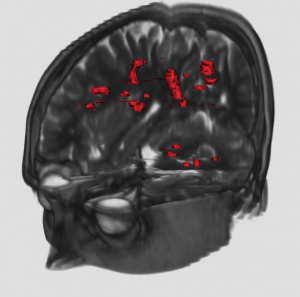

In radiotherapy treatment, the constant margin taken around the visible tumor is a very coarse approximation of the invasion margin of cancerous cells. This work tries to solve the problem of adapting the radiotherapy regions to the tumor growth dynamics. The method proposes approximate invasion margins of the tumor based on its growth dynamics. Determining radiotherapy regions based on these invasion margins would increase the effectiveness of the treatment. The low density tumor parts, undetectable by the current imaging techniques, are extrapolated in a magnetic resonance image (MRI). The extrapolation takes into account the underlying tissue structure (grey matter, white matter, fiber directions), the tumor growth dynamics approximated by the Fisher-Kolmogorov model and the segmented tumor in the image.

Segmentation of multimodal magnetic resonance images and application to multiple sclerosis

Multiple Sclerosis (MS) is an inflammatory disease of the Central Nervous System (CNS). Predominantly, it is a disease of the “white matter” tissue. In people affected by MS, patches of damage called plaques or lesions appear in seemingly random areas of the CNS white matter. At the site of a lesion, a nerve insulating material, called myelin, is lost. The quantification of the number of lesions, as well as their volume, could be of interest to assess the severity of the disease, and the success of a therapy. These lesions are of different types, and can not be all distinguished in one MR image: therefore, to better characterize them, several sequences are acquired (T1 weighted, with and without Gd, T2-weighted, PD-weighted). We are interested in developing classification and segmentation algorithms that will take advantage of all the available sequences to yield precise quantifications of the lesions in MS patients.

Multiple Sclerosis (MS) is an inflammatory disease of the Central Nervous System (CNS). Predominantly, it is a disease of the “white matter” tissue. In people affected by MS, patches of damage called plaques or lesions appear in seemingly random areas of the CNS white matter. At the site of a lesion, a nerve insulating material, called myelin, is lost. The quantification of the number of lesions, as well as their volume, could be of interest to assess the severity of the disease, and the success of a therapy. These lesions are of different types, and can not be all distinguished in one MR image: therefore, to better characterize them, several sequences are acquired (T1 weighted, with and without Gd, T2-weighted, PD-weighted). We are interested in developing classification and segmentation algorithms that will take advantage of all the available sequences to yield precise quantifications of the lesions in MS patients.

Automatic Detection and Quantification of Evolving Processes in 3D Medical Images

This work has been conducted mainly for the analysis of MR images of patients with Multiple Sclerosis. The goal (de circonstance!) is the design of new tools to help the clinicians to detect and locate new lesions, and also to measure objectively their evolution through time. To achieve this, we develop several approches (cf. publications). This work is done in collaboration with Harvard Medical School (Pr. Ron Kikinis) and with CHU of Nice (Pr. Chatel, Dr. C. Lebrun). Our work on automatic detection and quantification of evolving lesions deals essentially with:

This work has been conducted mainly for the analysis of MR images of patients with Multiple Sclerosis. The goal (de circonstance!) is the design of new tools to help the clinicians to detect and locate new lesions, and also to measure objectively their evolution through time. To achieve this, we develop several approches (cf. publications). This work is done in collaboration with Harvard Medical School (Pr. Ron Kikinis) and with CHU of Nice (Pr. Chatel, Dr. C. Lebrun). Our work on automatic detection and quantification of evolving lesions deals essentially with:

- pre-processings on MRI series (registration, intensity corrections, interpolation …)

- analysis of MRI evolutions. 2 methods have been developped: one based on the computation and on the analysis of a vector field of apparent displacement between 2 MRIs; the other based on a statistical analysis of the intensity evolution of each anatomical point over time.